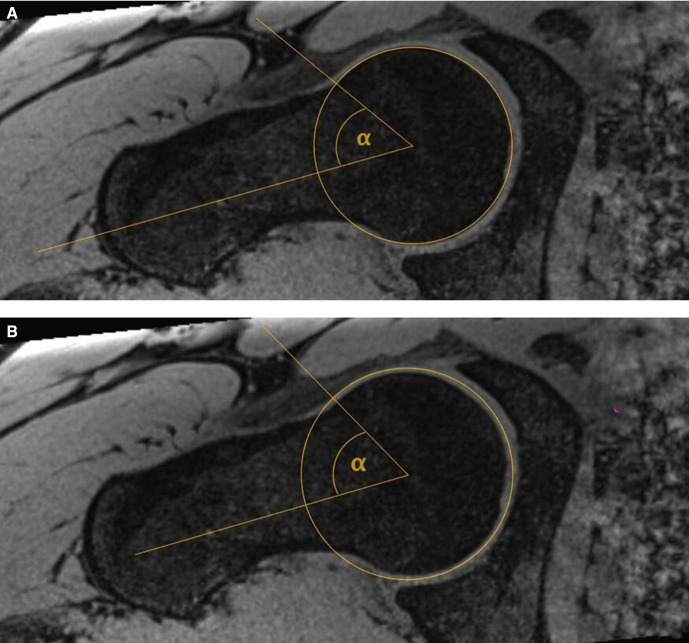

Cam morphology was quantified using the alpha angle for bone and cartilage (figure 1). Alpha angle was measured using custom-developed software on radial slices at 12 o’clock, 1 o’clock, 2 o’clock and 3 o’clock.16 The mean bone and cartilage alpha angle from 12 o’clock to to 3 o’clock were measured by an academic orthopaedic clinician (SF) blinded to participant information.9 Cam morphology was defined as an alpha angle of 60° or more in at least two MRI planes of a hip.17 18 All MRIs were reviewed for labral pathology and articular cartilage disease by a consultant musculoskeletal radiologist blinded to other participant information.

Figure 1.

Alpha angle measurement for bone (A) and cartilage (B) of the hip joint.